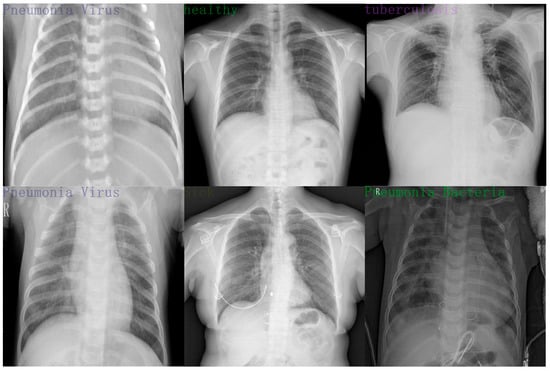

The previous experiments have already demonstrated the superior performance of the SFA-YOLO algorithm on the safety attire detection dataset. The MIMIC-CXR (MIMIC Chest X-ray) dataset is a publicly available collection of chest radiographs developed to facilitate research in medical image processing, disease diagnosis, and intelligent diagnostic systems. It comprises a large volume of accurately labeled X-ray images along with corresponding radiological reports, encompassing a wide spectrum of thoracic conditions, among which pneumonia is a key focus. The dataset includes more than 200,000 chest X-ray images that illustrate various pulmonary diseases such as pneumonia, tuberculosis, and pneumothorax, with most images originating from hospitalized patients. In total, 4194 images related to pneumonia were selected for detection purposes. This section further conducts experiments using a pneumonia detection dataset to evaluate the SFA-YOLO network’s generalization capability and analyze its detection performance on other public datasets. We used the open-source MIMIC Chest X-ray pneumonia dataset; the images were re-annotated using the LabelImg tool. As shown in Figure 9, the dataset contains five labels: Pneumonia Bacteria, Pneumonia Virus, Sick, Healthy, and Tuberculosis. To access the open-source MIMIC Chest X-ray pneumonia dataset, visit the following address: https://physionet.org/content/mimic-cxr/2.0.0/ (accessed on 1 January 2024).

Figure 9.

Pneumonia detection dataset.

Based on the results in Table 6, SFA-YOLO outperforms other YOLO-based algorithms on the pneumonia detection dataset. Although YOLOv7-Tiny and YOLOv5n achieve slightly higher precision, SFA-YOLO shows significantly better results in FPS, recall, mAP@0.5, and mAP@0.5:0.95. SFA-YOLO demonstrates a superior overall performance.

Higher recall reflects stronger sensitivity of SFA-YOLO to features and reduces missed detections, which holds greater importance in pneumonia diagnosis. Higher mAP@0.5 and mAP@0.5:0.95 indicate that SFA-YOLO maintains more robust detection performance under various conditions. Higher FPS ensures the more excellent practical value of SFA-YOLO in real-time detection scenarios.